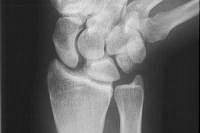

Final appearance of healed osteotomy.

Restoration of normal ulnar length.